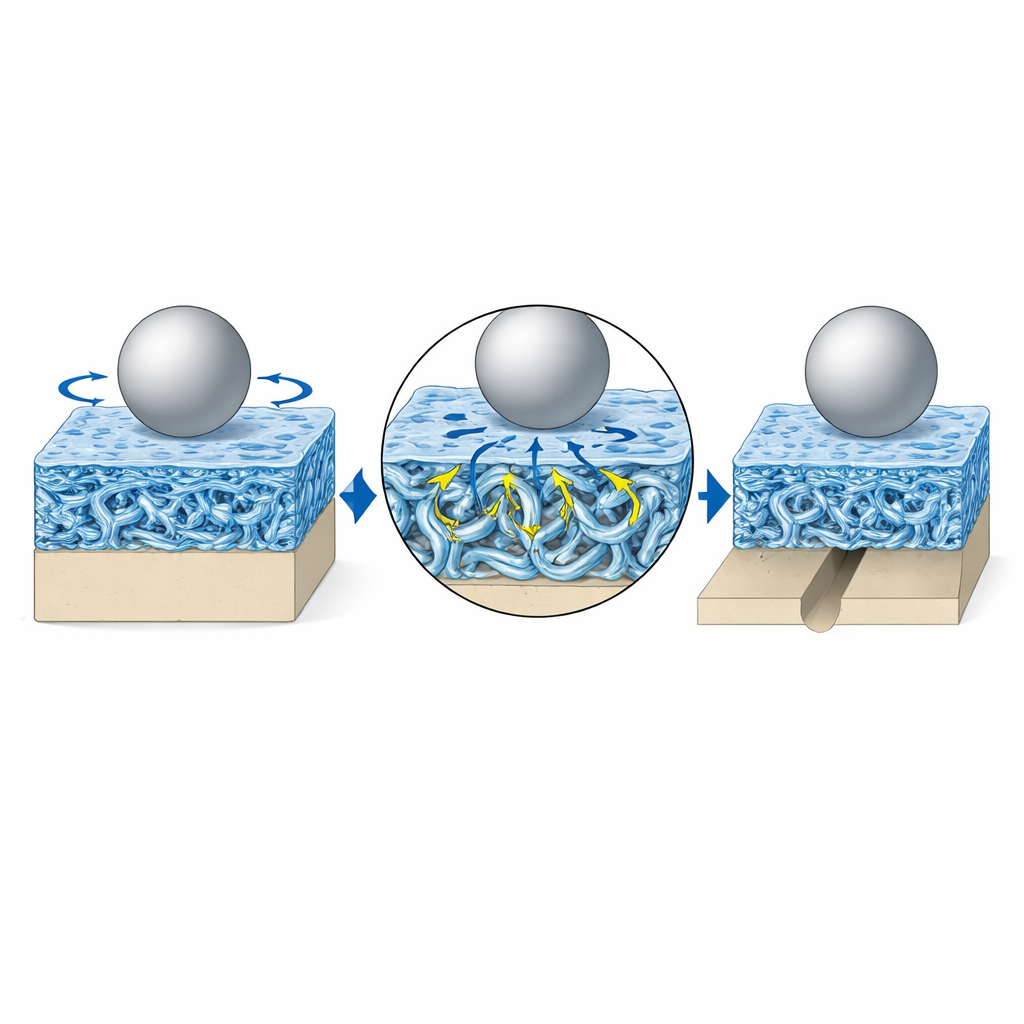

Il cuore della tecnologia è la cosiddetta rete di fibre picot. Queste fibre sono costruite da brevi catene peptidiche che si allineano in piccoli bastoncini, poi vengono cucite in una catena polimerica più lunga che forma anelli a forma di “picot” lungo il percorso. Quando il rivestimento viene compresso o stirato, questi anelli e i fasci peptidici possono dispiegarsi e allungarsi, assorbendo l’energia che altrimenti lacererebbe il materiale. Quando il carico viene rimosso, si richiudono e il materiale ritorna alla forma originaria. I test hanno mostrato che gli idrogel contenenti queste fibre picot possono estendersi molte volte rispetto alla loro lunghezza iniziale, resistere alla crescita di crepe per migliaia di cicli e recuperare quasi completamente dopo forti compressioni. Allo stesso tempo, la superficie rimaneva altamente idratata, conservando il suo carattere scivoloso.

Rimanere scivolosi sotto movimenti articolari realistici

Per riprodurre l’uso articolare, il team ha fatto scorrere una sfera metallica sulla superficie rivestita in una soluzione salina calda simile al fluido corporeo, per 100.000 cicli avanti e indietro sotto carichi comparabili a quelli di una salita a piedi. Il nuovo rivestimento ha mantenuto una frizione estremamente bassa — intorno a 0,009 — rivaleggiando o addirittura superando la cartilagine naturale, e ha mostrato quasi nessuna usura misurabile. Al contrario, la plastica nuda ha prodotto scanalature più profonde e frizione maggiore, e un rivestimento idrogel più semplice era inizialmente scivoloso ma si è rapidamente degradato, usurandosi più della plastica non rivestita. Il design a fibre picot ha anche distribuito la pressione di contatto su un’area più ampia, riducendo notevolmente gli stress massimi in superficie e contribuendo a proteggere sia il rivestimento sia il materiale dell’impianto sottostante.